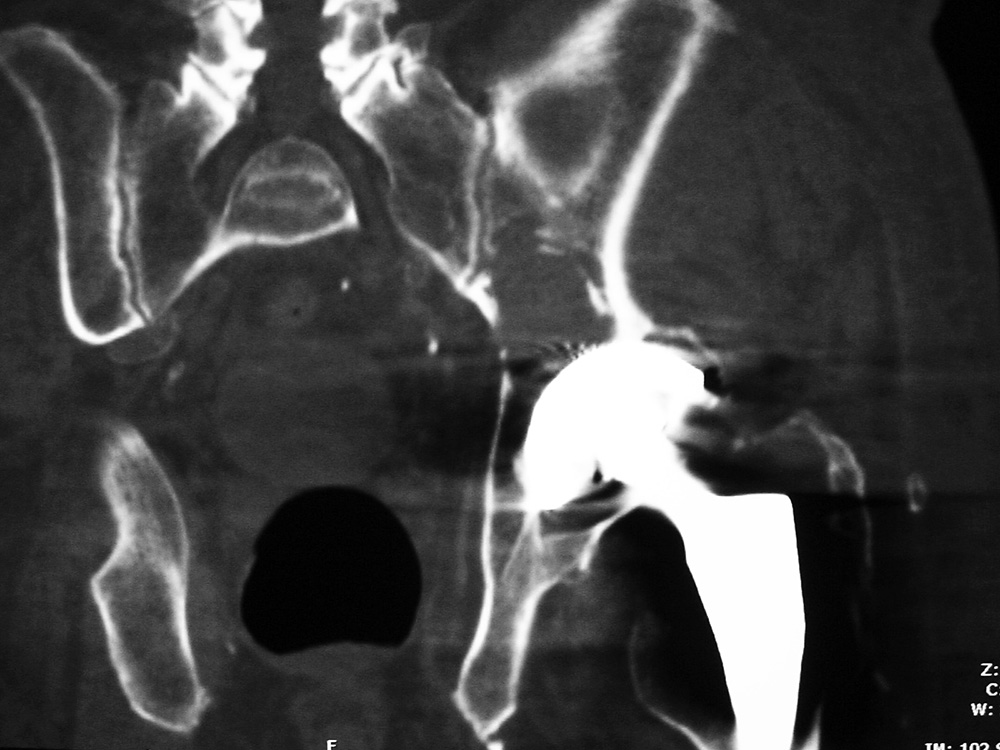

When local particulate matter becomes prominent and threatens or causes prosthesis failure, it is called particle disease or metallosis (figure: particle disease in right hip implant; figure: particle disease left hip CT; figure: left hip polyethylene liner wear; figure: metal-on-metal prosthesis with metallosis). See the discussion of adverse reaction to metal debris in Orthopedic medical devices and cross-sectional imaging: protocols and artifacts - MRI.

Particle disease (arrows) left hip coronal CT image |

68 year-old man with particle disease from a worn out left hip prosthesis. Bony destruction (arrows) is in the left supra-acetabular region and in the left greater trochanter with a pathologic fracture. |